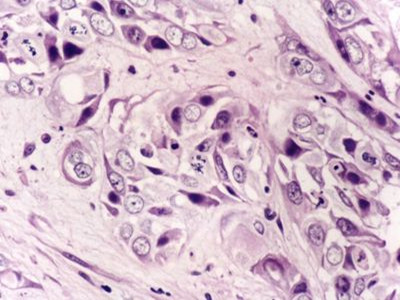

细胞分裂或细胞增殖是普遍发生在许多组织的一个生理过程。通常细胞增殖和细胞凋亡会达到平衡,而且受到严谨地调控以保证器官和组织的完整性。DNA的突变或是经遗传得到的缺陷基因导致这些有序的过程受到改变。

随着细胞生长复制,如同滚雪球般持续累积新突变,最终不受管制而增殖的细胞通常会转变成良性肿瘤或恶性肿瘤。

良性肿瘤不会扩散到身体其他部份,或是侵入别的组织,除非压迫到重要的器官,否则也不会影响生命。恶性肿瘤则会侵略其他器官,转移到身体其他部位而危害生命。